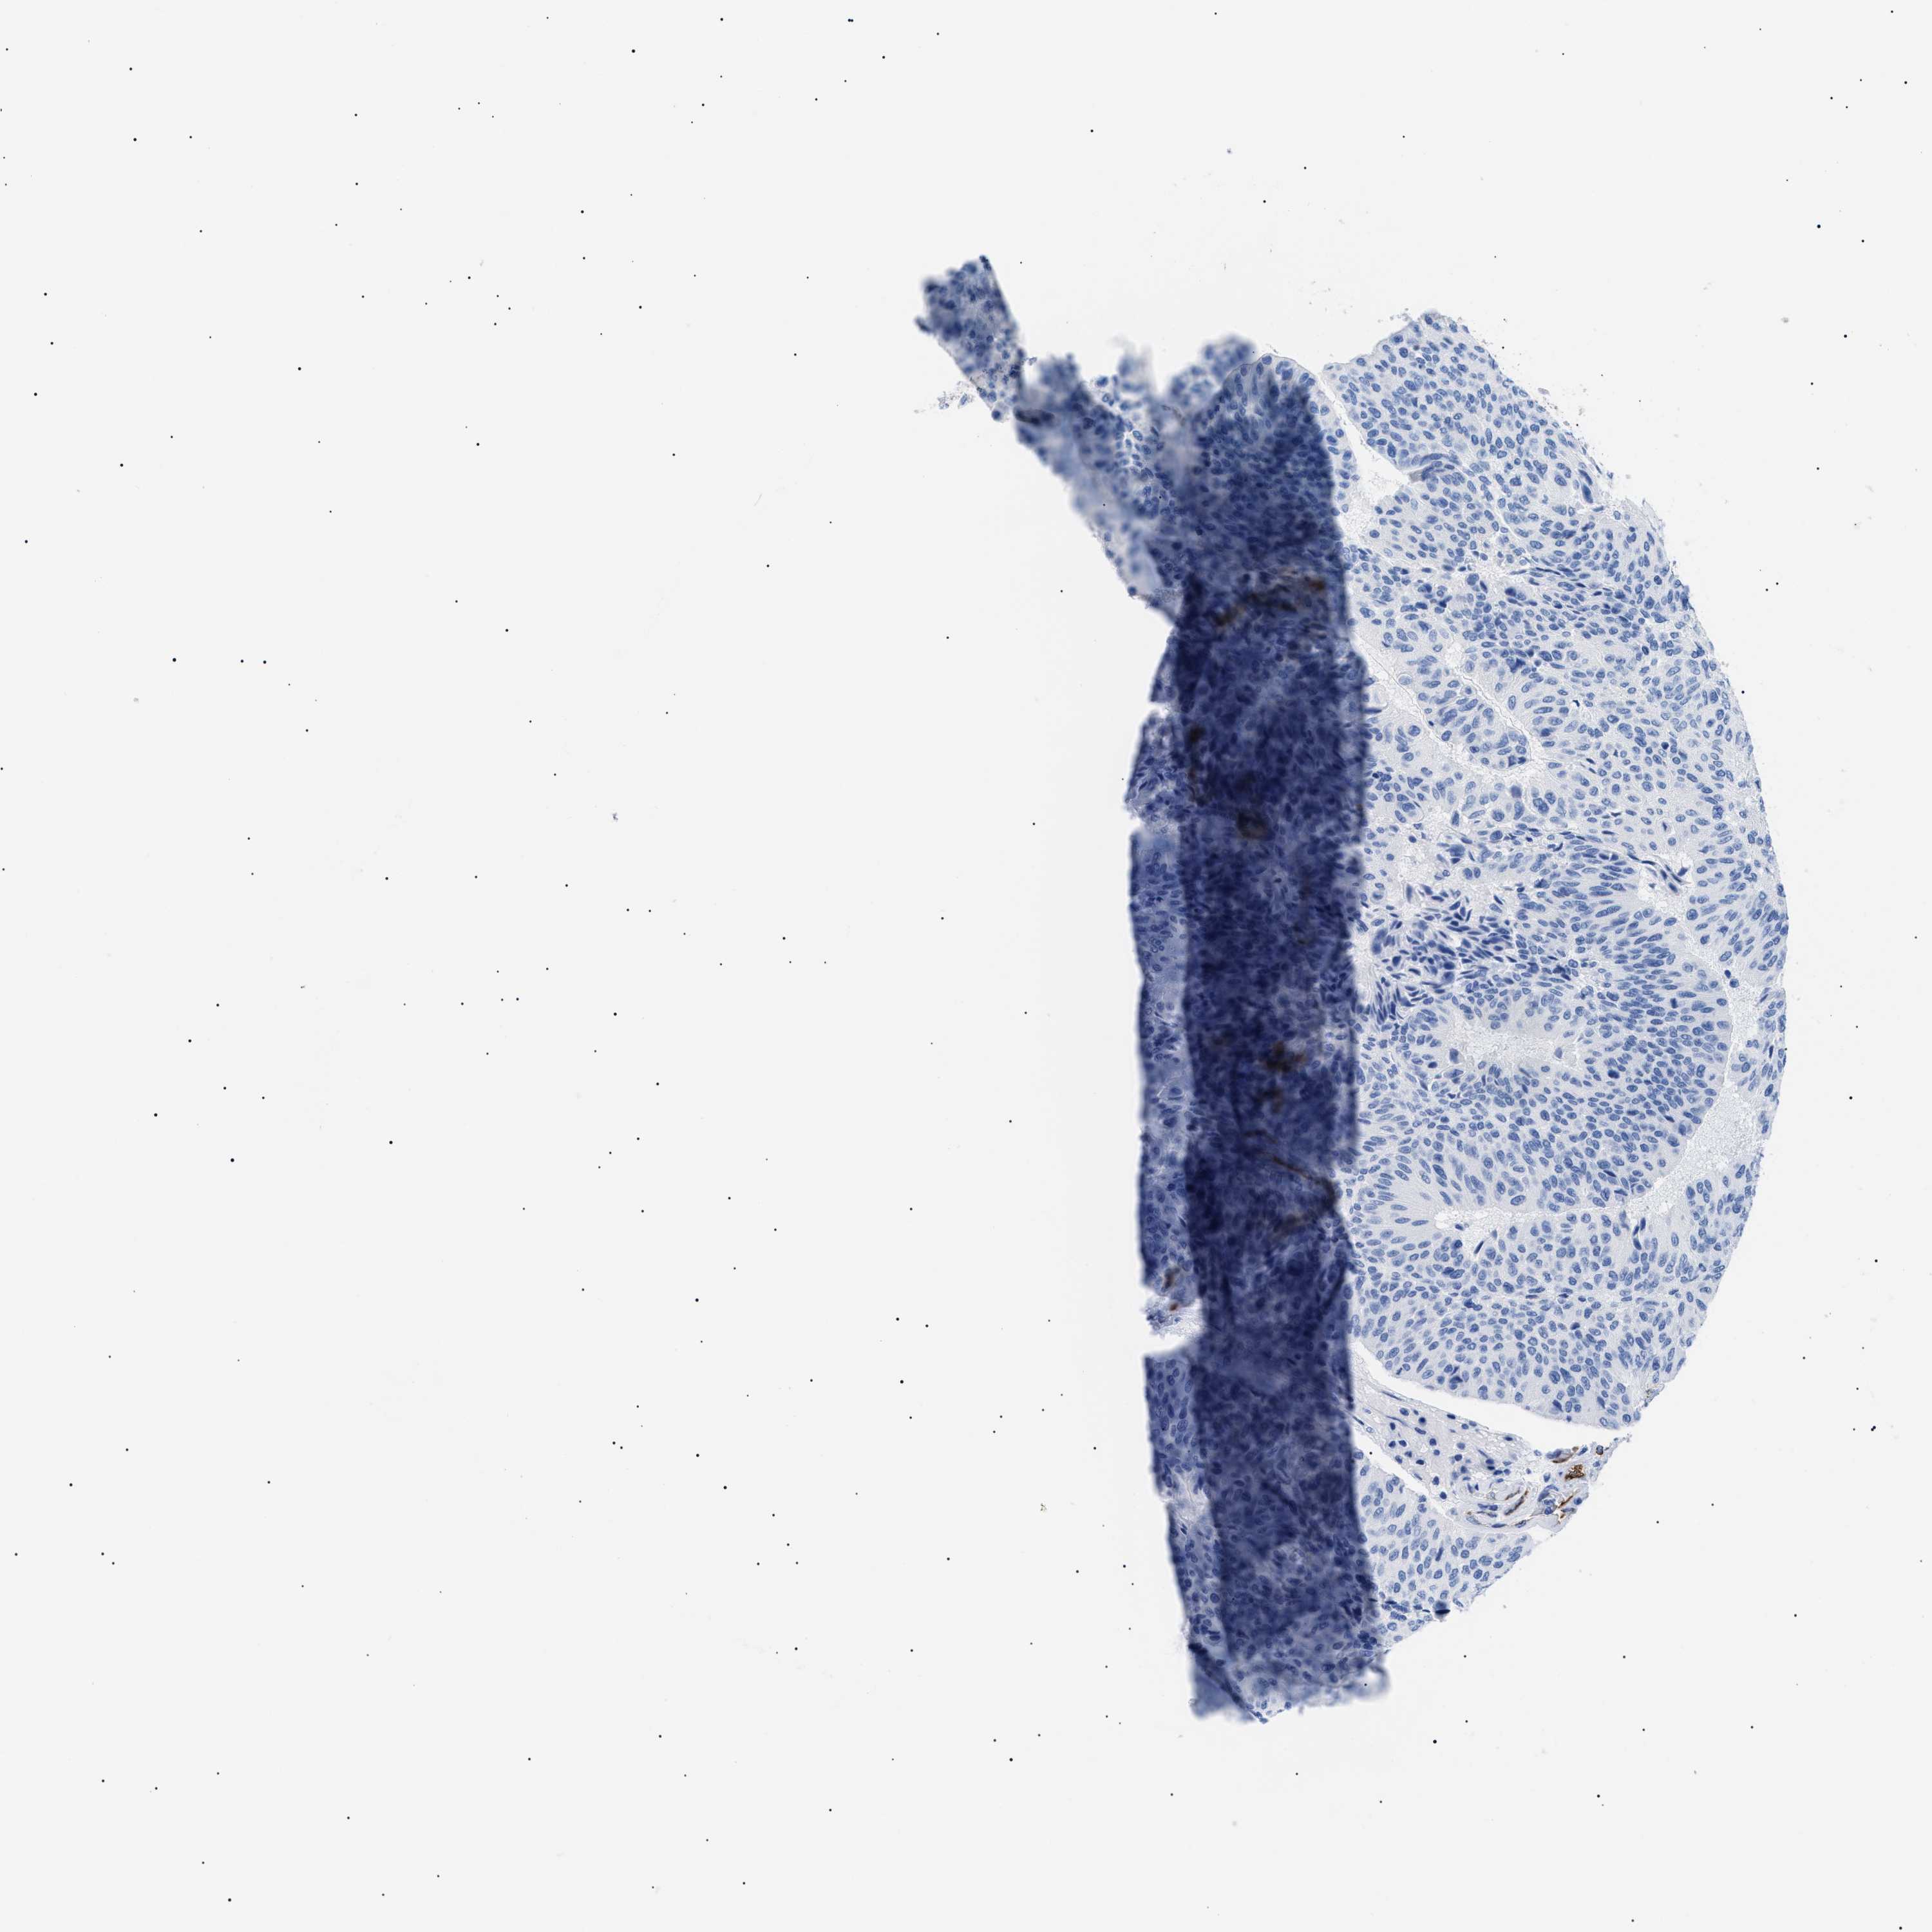

UROTHELIAL CANCER - Protein expressioni

A mouse-over function shows sample information and annotation data. Click on an image to view it in a full screen mode. Samples can be filtered based on level of antibody staining by selecting one or several of the following categories: high, medium, low and not detected. The assay and annotation is described here.

Antibody stainingi

Antibody staining in the annotated cell types in the current human tissue is reported as not detected, low, medium, or high, based on conventional immunohistochemistry profiling in selected tissues. This score is based on the combination of the staining intensity and fraction of stained cells.

Each image is clickable and will lead to virtual microscopy that enables deeper exploration of all samples and also displays staining intensity scores, fraction scores and subcellular localization as well as patient and tissue information for each sample.

HPA002110

HPA045507

CAB016169

CAB062558

CAB068219

CAB068220

Staining

High

Medium

Low

Not detected

Intensity

Strong

Moderate

Weak

Negative

Quantity

>75%

75%-25%

<25%

None

Location

Nuclear

Cytoplasmic/membranous

Cytoplasmic/membranous,nuclear

Urothelial carcinoma, High grade

Urothelial carcinoma, NOS

Urothelial carcinoma, Low grade